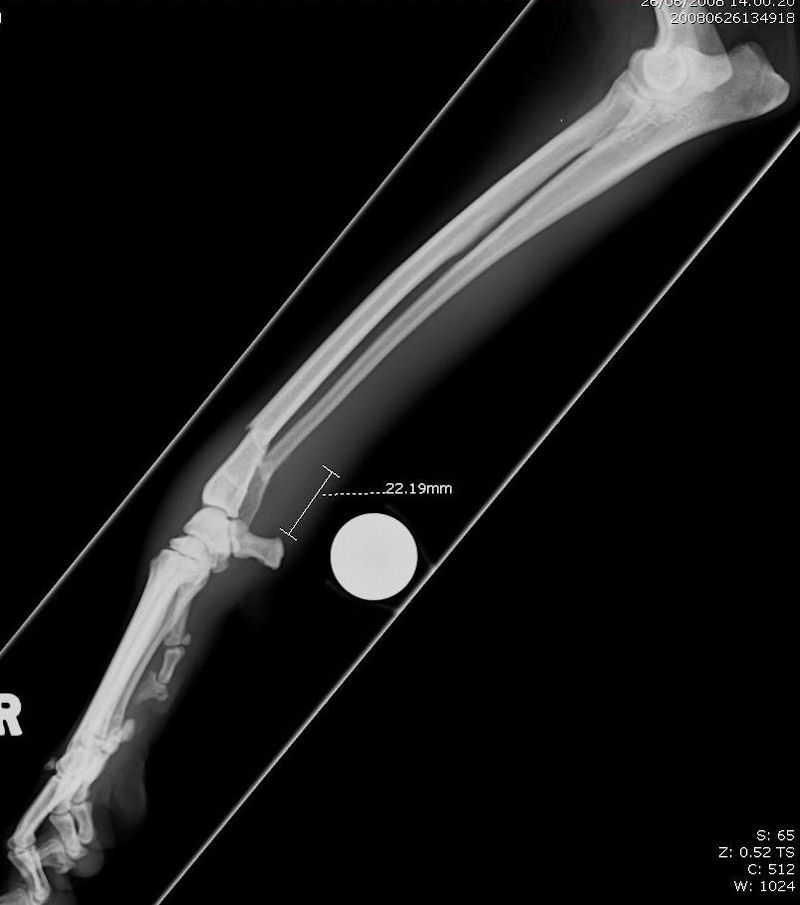

Dog X Ray Showing Radius and Ulna Fracture. Lateral View Stock Photo Radius/Ulna Fracture Dog Surgery 1) any toy breed dog with a radius and ulna fracture should undergo surgical fixation, usually rigid internal fixation, and should not be treated with a cast or a splint. Traumatic radius and ulna (antebrachial) fractures are common in dogs and cats and often require surgical treatment for optimal outcome (figure 14.1). Distal radius and ulna fractures. Result from falls. Radius/Ulna Fracture Dog Surgery.

Dog X Ray Showing Radius and Ulna Fracture. Lateral View Stock Photo Radius/Ulna Fracture Dog Surgery Although various techniques can be used for the treatment of radius and ulna fractures in small breed dogs, bone plating remains one of the. In an attempt to improve fracture management, künthscher established the foundations of minimally invasive fracture. Traumatic radius and ulna (antebrachial) fractures are common in dogs and cats and often require surgical treatment for optimal outcome (figure. Radius/Ulna Fracture Dog Surgery.